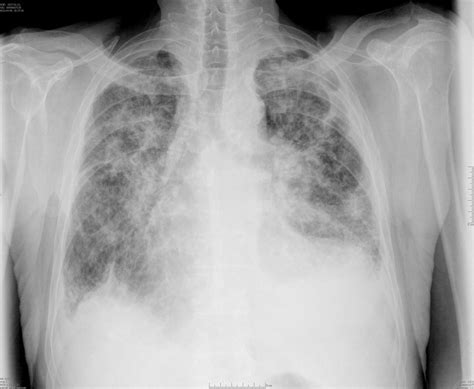

So, when we talk about the batwing appearance in radiology , we’re primarily referring to a specific pattern seen on a chest X-ray or CT scan. Imagine a bat spreading its wings – that’s kind of the shape we’re looking for. This pattern typically shows increased opacity, meaning it looks whiter and denser than normal lung tissue, predominantly in the central areas of both lungs. These opacities often radiate outwards from the hilum, which is the central part of the lung where blood vessels and airways enter and exit, giving it that characteristic wing-like spread. It’s like a shadow that’s thicker near the middle and thins out as it goes towards the edges of the lungs. This distribution is key; it’s not a random smattering of white spots but a more organized, symmetrical pattern. The central location and outward spread are what make radiologists sit up and take notice. It’s a visual cue that something is happening in those specific parts of the lungs. Think of it as the lungs trying to tell us a story, and the batwing appearance is a significant chapter in that story. The symmetry is often emphasized, meaning both lungs tend to show this pattern to a similar degree, though variations can occur. This bilateral and central distribution helps differentiate it from other lung abnormalities that might be more peripheral or asymmetrical. It’s a pattern that radiologists are trained to spot, and once seen, it prompts further investigation into its underlying cause. The density can vary, from subtle haziness to more pronounced white areas, but the core pattern of central, radiating opacity remains the hallmark.

The batwing appearance in radiology isn’t just a random finding; it’s a symptom of various underlying conditions, most commonly related to fluid buildup in the lungs. The most classic culprit is pulmonary edema , which is essentially excess fluid in the lung tissue. When the heart isn’t pumping efficiently (think heart failure), fluid can back up into the lungs. This fluid tends to accumulate first in the most dependent and well-perfused parts of the lungs, which are often the central areas near the hilum. Another major player is acute respiratory distress syndrome (ARDS) . ARDS is a severe lung condition where fluid leaks into the tiny air sacs (alveoli) of the lungs, making it hard to breathe. The widespread inflammation and leakage in ARDS can also lead to this characteristic central opacity. Pneumonia, especially certain types like viral or atypical pneumonia, can sometimes present with a batwing pattern. The infection causes inflammation and fluid in the airspaces, and if it affects the central lung regions symmetrically, it can mimic this appearance. Certain rarer conditions, like pulmonary hemorrhage (bleeding into the lungs) or even some forms of interstitial lung disease, might also contribute to a batwing pattern, though these are less common associations. It’s crucial to remember that the batwing appearance is a description of a pattern, not a diagnosis in itself. It’s like seeing smoke – you know there’s a fire somewhere, but you need to investigate to find out exactly where and why. The radiologists look at this pattern and then correlate it with the patient’s symptoms, medical history, and other clinical findings to arrive at a specific diagnosis. The distribution points to a process that is affecting the lung interstitium and alveolar spaces in a diffuse, yet centrally predominant, manner. This can be due to increased hydrostatic pressure (as in heart failure), increased permeability of the alveolar-capillary membrane (as in ARDS or severe pneumonia), or direct injury to the lung tissue. The symmetry often suggests a systemic cause or a process affecting both lungs equally from the outset, rather than a localized injury or infection.

Pulmonary Edema and the Batwing Sign: A Classic Connection

When radiologists see that distinct batwing appearance in radiology , one of the first things that often springs to mind is pulmonary edema , particularly cardiogenic pulmonary edema. This is when fluid leaks out of the blood vessels and into the air sacs and tissues of the lungs, usually because the heart isn’t pumping blood effectively. In cases of heart failure, the pressure in the blood vessels of the lungs increases, pushing fluid out. This fluid tends to accumulate preferentially in the central and lower portions of the lungs, areas that are generally more well-perfused and have higher pressures. The resulting opacities on the X-ray or CT scan can form that classic batwing shape, with the densest areas hugging the heart and major airways, and tapering off towards the periphery. It’s like the lungs are getting waterlogged, and the water spreads out from the central plumbing. It’s a really common scenario, and seeing the batwing pattern strongly suggests this diagnosis, especially if the patient presents with symptoms like shortness of breath, coughing up pink, frothy sputum, or swelling in their legs. The symmetry of the batwing appearance is also characteristic of cardiogenic edema, as the increased pressure affects both lungs relatively equally. While other causes of edema exist, the heart-related kind is the most frequent association with this specific radiological pattern. This connection is so strong that the term